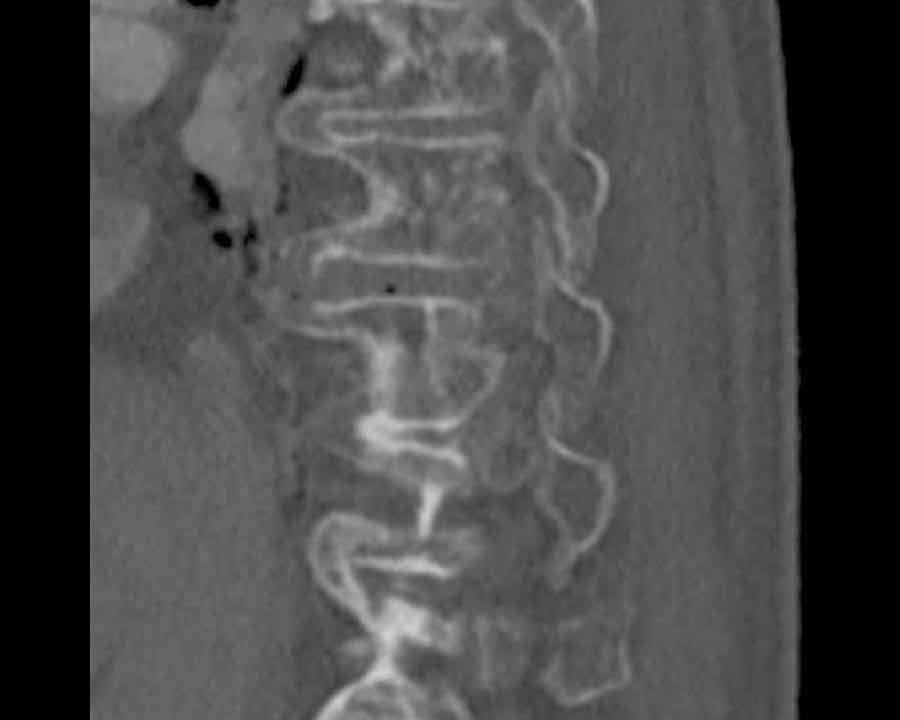

Scroll through images.

What are the findings?

Findings

- C injury? No.

- Signs of a rigid spine?

Yes (DISH), so a B3 injury is very likely. - A subtle fracture on the anterior vertebral body (arrows).

- No separation, probably due to positioning of patient in the scanner

Conclusion

Injury type B3.